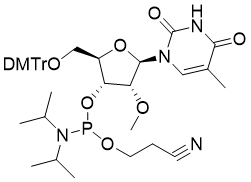

馬鞍山致研生物醫(yī)藥科技有限公司成立于馬鞍山市鄭浦港新區(qū)現(xiàn)代產(chǎn)業(yè)園。公司專(zhuān)注于生物小分子、醫(yī)藥中間體相關(guān)產(chǎn)品的研發(fā)和生產(chǎn),產(chǎn)品主要包括DNA亞磷酰胺單體、RNA亞磷酰胺單體、特殊單體以及按照客戶(hù)要求定制的RNA和DNA,并且公司提供定制合成等方面的研究服...

馬鞍山致研生物醫(yī)藥科技有限公司成立于馬鞍山市鄭浦港新區(qū)現(xiàn)代產(chǎn)業(yè)園。公司專(zhuān)注于生物小分子、醫(yī)藥中間體相關(guān)產(chǎn)品的研發(fā)和生產(chǎn),產(chǎn)品主要包括DNA亞磷酰胺單體、RNA亞磷酰胺單體、特殊單體以及按照客戶(hù)要求定制的RNA和DNA,并且公司提供定制合成等方面的研究服...